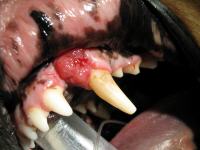

Max ist ein 10 Jahre alter Golden Retriever, der bei uns in der Praxis 2005 wegen eines Geschwüres im Oberkiefer vorgestellt wurde.

Zuerst wurde eine Probe entnommen und zur weiteren Untersuchung an einen Pathologen zur Auswertung gesendet.

Das Ergebnis war leider erschreckend, da es sich um einen bösartigen Tumor handelte, welcher so schnell wie möglich entfernt werden musste. Max bekam einen Termin zur Operation.